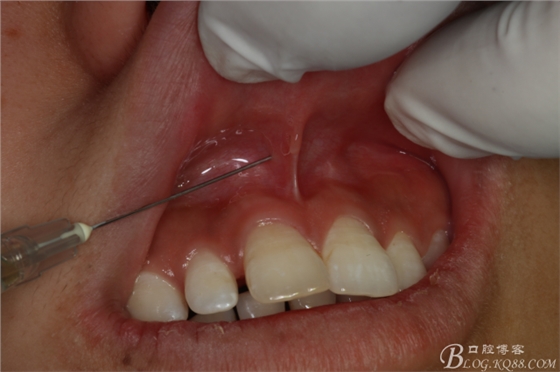

圖5.唇、腭側(cè)局部無(wú)痛浸潤(rùn)麻醉